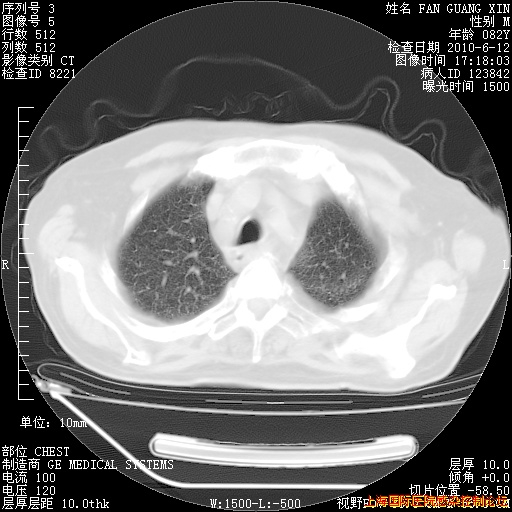

补发6月12日肺部CT肺窗

6月12日肺窗